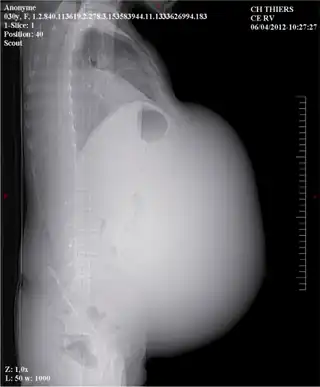

Mucinous borderline tumor: Preoperative appearance of the abdominal distension -